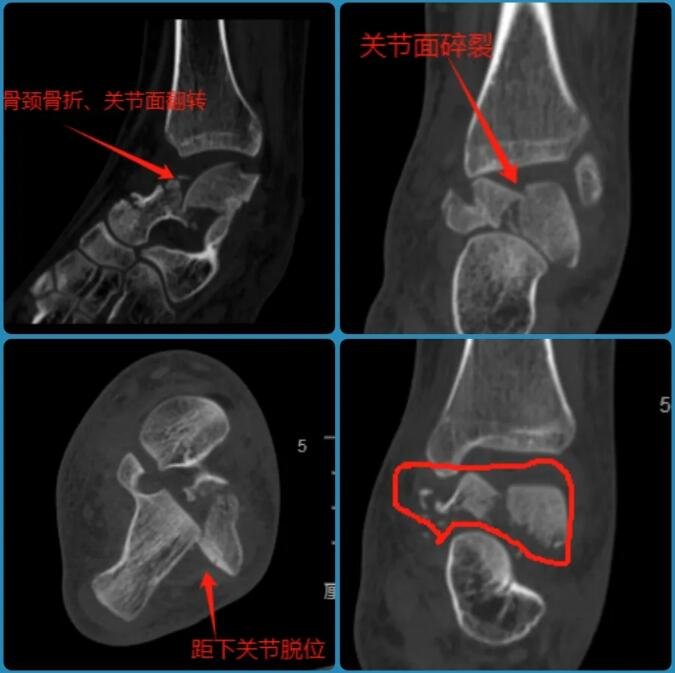

今年9月底的一天,14岁的小蕊不幸从三楼坠落到水泥地面上,造成腰椎前、中、后三柱骨折,双侧足踝粉碎性骨折,尤其是左踝距骨碎成了很多块。如此严重的伤情,很可能导致小蕊后半生在轮椅上度过。

△小蕊左踝伤处透视影像。